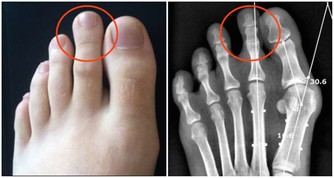

常見的腳氣有3種型,症狀各不相同:

浸漬糜爛型:足部糜爛發白,常長在趾縫,特別是3、4及4、5腳趾縫間;

水皰型:足底足側,長水皰,乾涸後脫屑;

鱗屑角化型:足底足跟,乾燥脫屑皸裂,常常對稱分佈。可能不臭不癢。